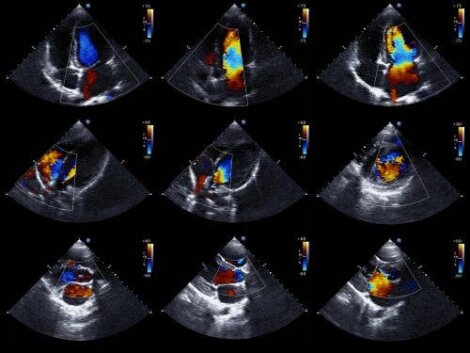

Benché un aspetto a fiasco dell'ombra cardiaca possa essere dimostrato con una radiografia del torace, questa metodica pone dei problemi di diagnosi differenziale con la cardiomegalia che si può avere, ad esempio, in corso di insufficienza cardiaca. La metodica più sensibile e specifica risulta essere l'ecocardiografia, attraverso la quale è possibile identificare il versamento come uno spazio ecoprivo tra le pareti cardiache e il pericardio. Attraverso l'ecocardiografia è inoltre possibile quantificare l'entità del versamento pericardico, valutando la cinetica ventricolare e la riduzione delle pulsazioni ventricolari e il rapporto con le fasi della respirazione. Attraverso la misura ecocardiografica del diametro antero-posteriore del sacco pericardico è possibile prevedere la quantità di liquido pericardico presente, in modo da programmare una possibile pericardiocentesi. La TC e RMN consentono di visualizzare un eventuale ispessimento delle pareti pericardiche o versamenti difficilmente apprezzabili.